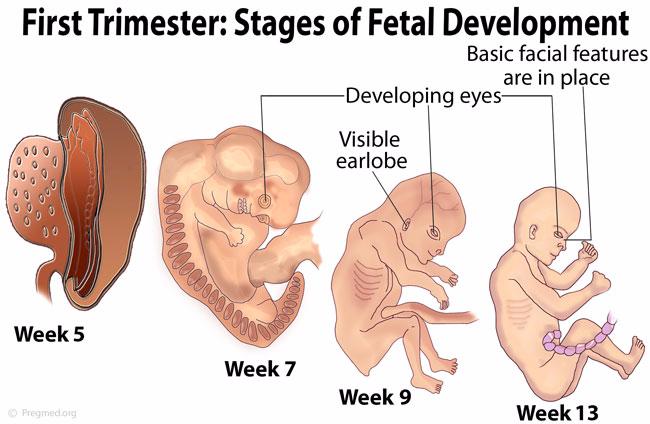

Формирование Плода в Первом Триместре: Важные Этапы